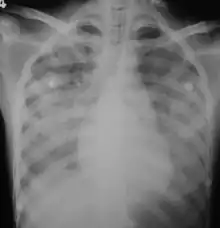

In those who have lung involvement, a chest X-ray may demonstrate diffuse alveolar opacities.[16]